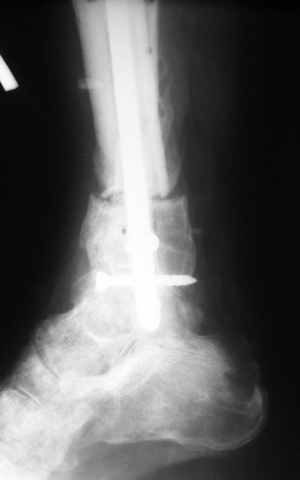

В случае гладкого заживления раны, при условии положительного решения вопроса с металлом, планируем перемонтаж аппарата Илизарова, дополнительную резекцию дистального отломка, выведение полокости голеностопного сустава в правильное положение (см. боковую Р-грамму), одномоментно остеотомия большеберцовой кости. После восстановления длинны голени, по всей видимости, артродез голеностопного сустава.

Рентгенограммы прилагаются. Фото местного статуса выложу в ближайшее время.

Мы обычно не фиксируем малоберцовую кость. Просто стараемся сопоставить ее концы за счет хорошей репозиции. В представленном случае имеется некоторое смещение дистальных фрагментов кнаружи, и, как мне кажется, ротация их вместе со стопой кнутри (ротация хорошо заметна на прямом снимке по форме таранной кости и на боковом по соотношению отломков малоберцовой). Если это действительно так, то это несложно сейчас постепенно устранить в аппарате. И тогда концы малоберцовой кости будут находиться поближе друг к другу.